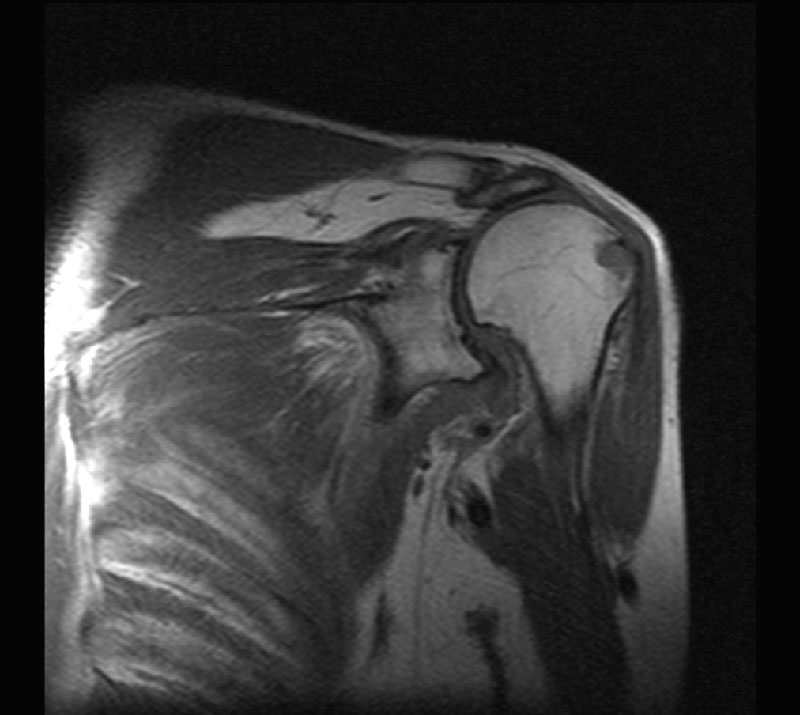

Специфика строения мягких тканей, включая суставную и слизистые сумки, мышечно-связочный аппарат, хрящевой компонент суставной губы делают МРТ исследование незаменимым при диагностике плечевого сустава, особенно если речь идет о травме.

Все, что можно обнаружить при МРТ плеча, специалист, проводящий исследование, дифференцировано оценивает на многочисленных сканах, дающих объемное представление о состоянии каждого из анатомических элементов.

Что покажет МРТ плечевого сустава

Дегенеративные заболевания (артрит и артроз)- Переломы (скрытые), состояние вывиха и подвывиха головки плеча

- Повреждения вращательной манжеты, которые являются основной причиной болей в области плеча, в особенности у пациентов старшей возрастной группы

- Разрывы связок и сухожилий, надрыв суставной губы (повреждение Хилла-Сакса и Банкарта) *

- Спортивные травмы и травмы связанные со специфической работой (вибрационные установки, механизированные системы)

- Инфекции (остеомиелит)

- Асептический некроз головки плечевой кости (в особенности при наличии у пациента системных заболеваний - системная красная волчанки, ревматоидный артрит)

- Опухоли костные / мягких тканях

- Отложение солей кальция в области мягких тканей плеча (кальцификаты)

- Синовит (воспаление внутренней оболочки полости сустава)